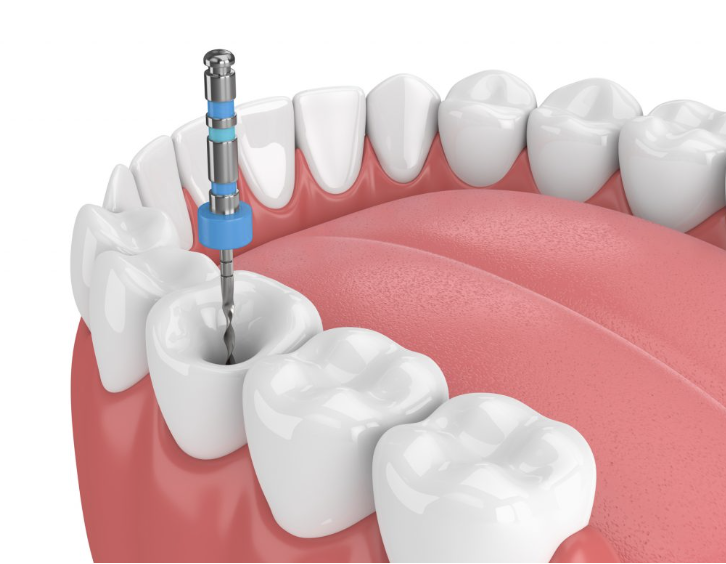

Endodoncia

La endodoncia es un procedimiento que tiene como finalidad preservar las piezas dentales dañadas, evitando así su pérdida. Para ello, eliminamos el tejido enfermo del diente extrayendo la pulpa dental y la cavidad resultante, se rellena y sella con material inerte y biocompatible de forma que se pueda conservar la pieza.